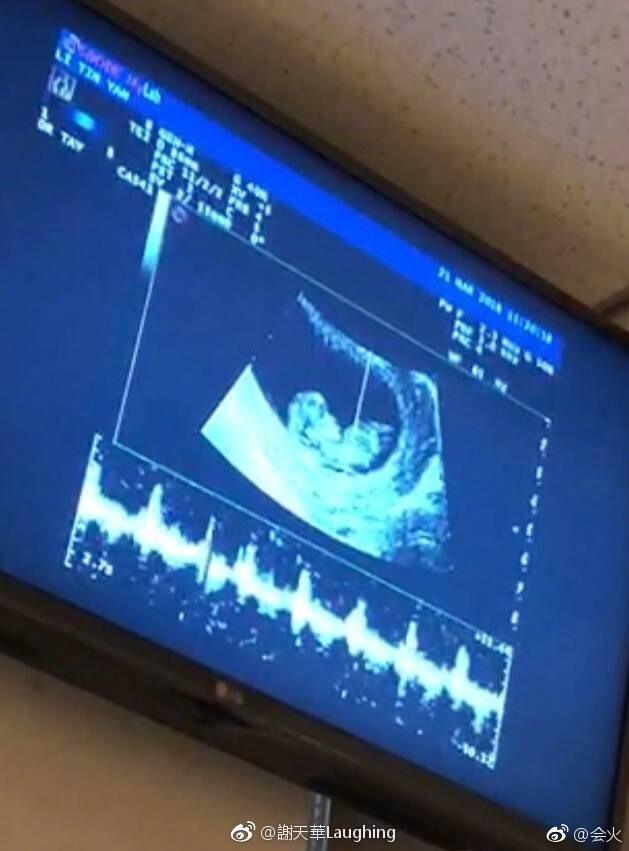

原标题:丁俊晖晒女儿小脚丫宣布升级当爸爸:顺产母女平安丁俊晖升级当爸腾讯体育讯北京时间8月8日晚,尽管

8日晚,著名斯诺克选手丁俊晖 在今年4月微博发文宣布升级当爸。2018年4月9日,丁俊晖宣布即将成为父亲;据悉

丁俊晖升级当爸,北京奥运会十周年这一天出生,一位九球天后诞生!丁俊晖,宣布妻子于18年8月8日顺产得女,

丁俊晖升级当爸 8日对于中国台球名将丁俊晖来说无疑是幸福的一天,他在当晚宣布自己喜迎爱女,正式升级到

丁俊晖升级当爸,尽管在江西玉山进行的2018斯诺克世界公开赛第二轮中不敌米尔金斯出局,但8日对于中国台球